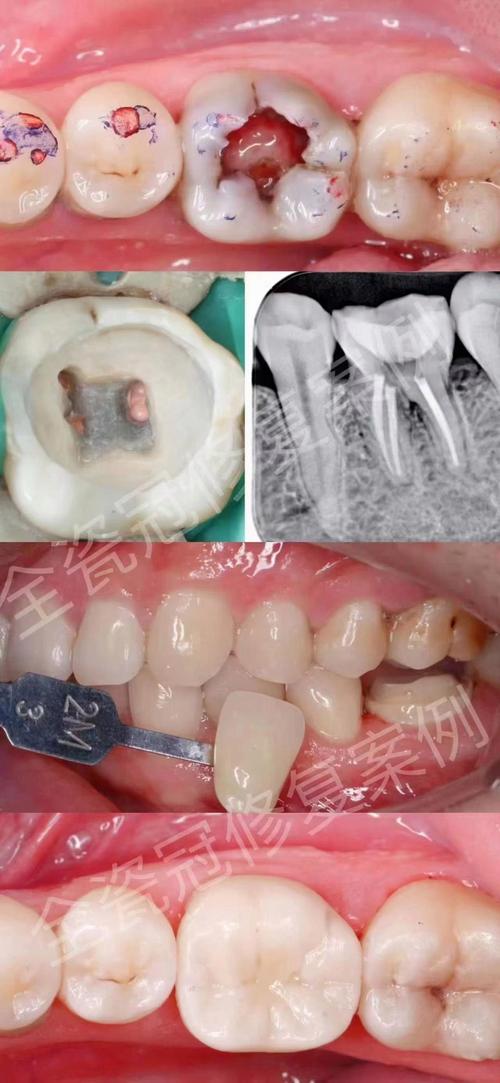

- 牙齿被保留,进行桩核冠修复(最常见)

- 这是最理想的情况。 如果根管治疗后的牙齿牙根足够坚固、没有大面积龋坏或折裂,并且有足够的牙槽骨支持,医生通常会建议保留这颗牙齿。

- 如何修复: 在牙根内打入一个桩核(金属或纤维桩),然后在桩核上制作一个牙冠(全瓷、烤瓷等),这样就能恢复牙齿的外形、功能和美观。

- 种植牙的必要性: 在这种情况下,不需要进行种植牙,这颗经过桩核冠修复的牙齿可以继续行使功能。